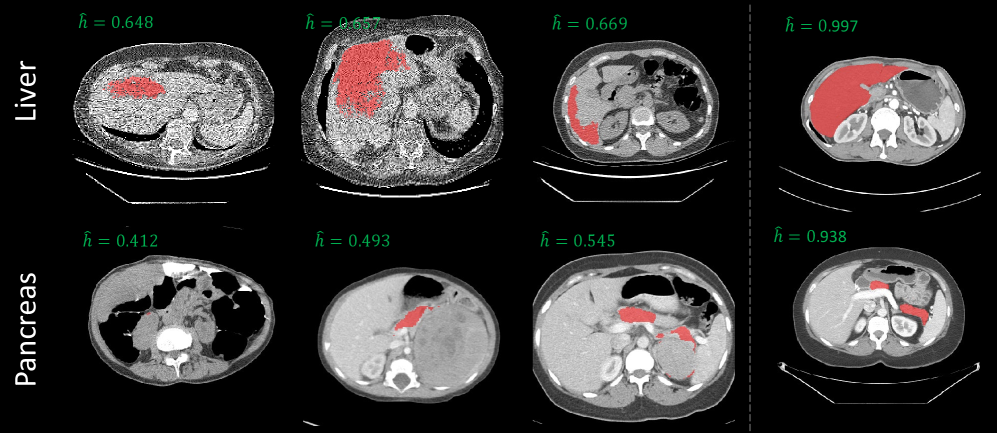

SegAE highlights typical issues such as reduced, missing, and expanded masks (Fig. 4) in AbdomenAtlas [li2024abdomenatlas]. We conducted a quantitative benchmarking of 6 segmentation datasets focusing on major abdominal organs using SegAE, as detailed in Tab. 2. We observed that smaller human-annotated datasets, exhibit superior organ-wise label quality. Conversely, in larger datasets like TotalSegmentator and AbdomenAtlas, there is a noticeable decline in the overall DSC estimation and more low quality labels with . SegAE reveals low-quality labels (DSC ¡ 0.8) in large mixed-source datasets, motivating further re-annotation. After SegAE’s filtering and human screening, DAP Atlas presents a large improvement on label quality .